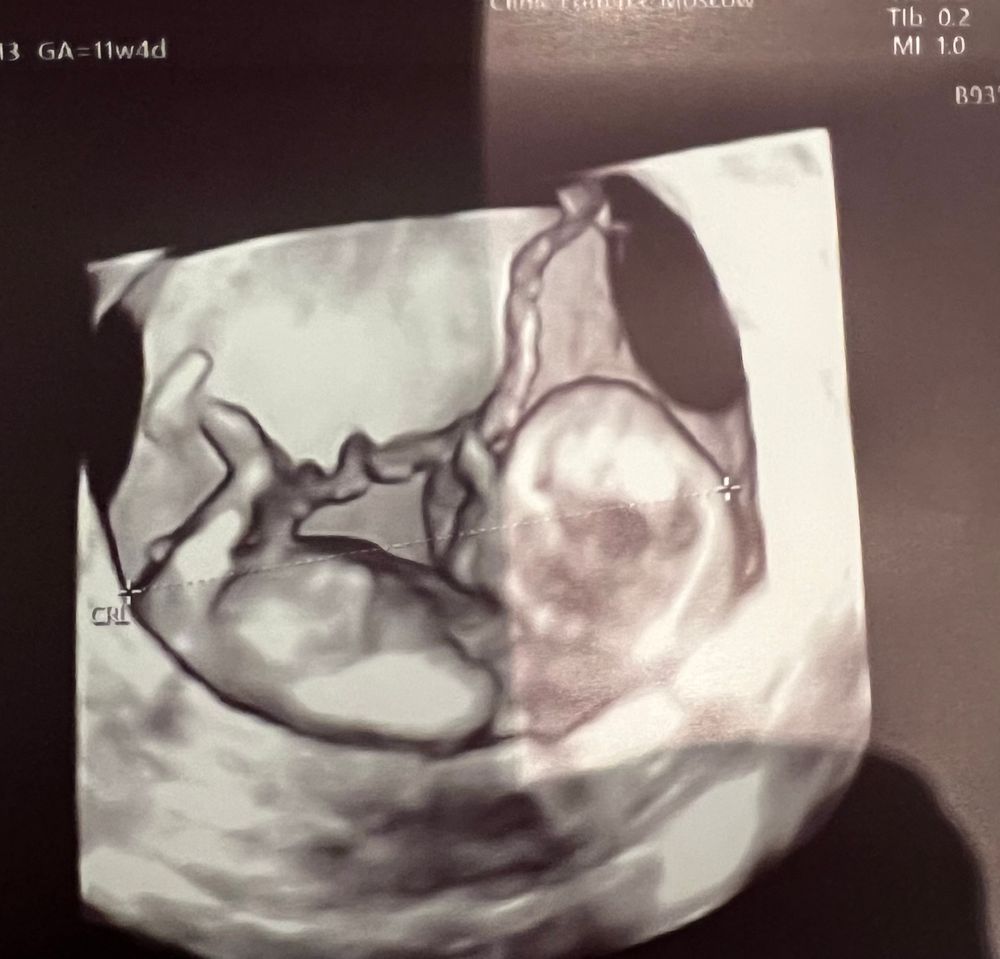

Можно ли увидеть пол? Фото

Это девочка, пениса и яичек ещё нет, есть половой бугорок. Он здесь параллельно позвоночнику, значит это девочка.

У Вас бугорка здесь нет, потому что его закрыла ножка. На таком сроке сложно сказать, мне кажется, что у Вас мальчик, но это это могут быть и половые губы в такой стадии формирования, так что ясно станет через несколько недель.